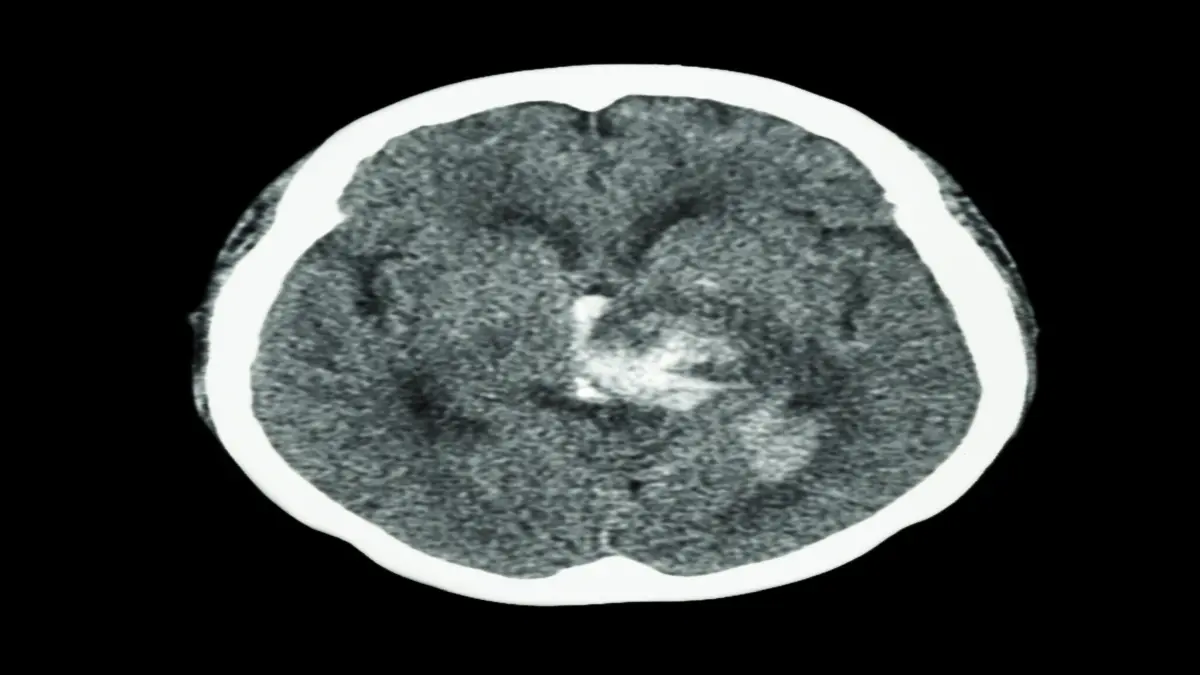

🔒 Intrazerebrale Blutungen: Vorgehen in Notfall- und Intensivmedizin